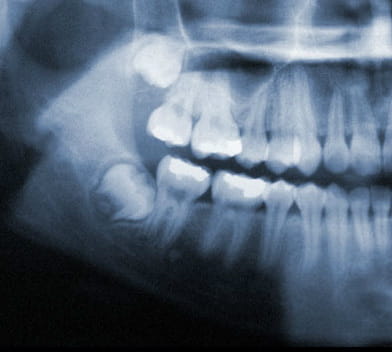

Wisdom Tooth Positions

Wisdom teeth under ideal circumstances should grow in straight like any other tooth. However, it is common for wisdom teeth to become impacted inside the jaw or just under the gums. If this occurs, your wisdom teeth should be removed.

Common Impactions:

- Horizontal Impaction

- Angular Impaction

- Vertical Impaction

- Soft Tissue Impaction

The problems involving your wisdom teeth may be caused by the size of your jaw and/or by how crowded your teeth are. Common warning symptoms that there is an un-natural problem in the development of your wisdom teeth could be pain and swelling.

Wisdom teeth also known as third molars are the last teeth to erupt into the mouth. Wisdom teeth typically appear around a person's mid-twenties but can erupt much later. If wisdom teeth don't have enough space symptoms can occur. The wisdom teeth may only partially erupt or might not come through at all. Dentists designate wisdom teeth 'impacted' if they are wholly or partly blocked from eruption into the mouth. The tooth may lie at an angle and remain tipped against an adjacent tooth. Impacted wisdom teeth can cause problems like pain and swelling; The mouth could ache when stretched open wide or it may be difficult to open your mouth. Tenderness when chewing and biting may occur. Earaches may develop from the spread of pain in the mouth. Symptoms may be intermittent but can begin anytime without warning. If you are experiencing symptoms, it is best to get treatment 'usually removal' as soon as you can to avoid potentially expensive and painful complications.